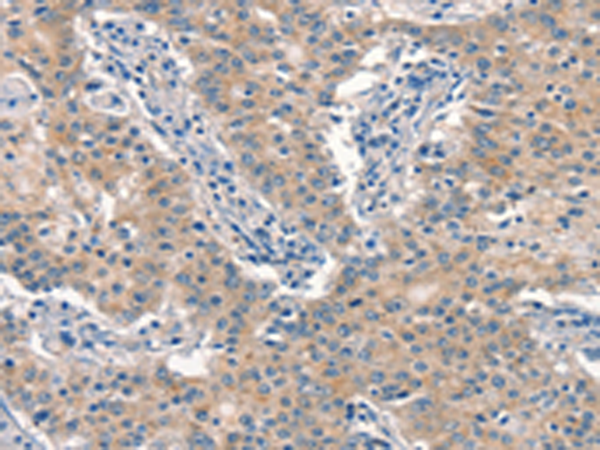

分类: 科研抗体货号: P04845别名: p43; HLD3; EMAP2; SCYE1; EMAPII应用: WB,IHC反应种属: Human, Mouse